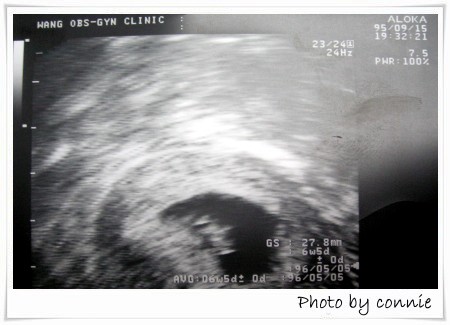

第一次產檢:

日期:95年9月15日

週數:7周+

抽血驗血型,血紅素,驗尿

預產期:96年5月3日